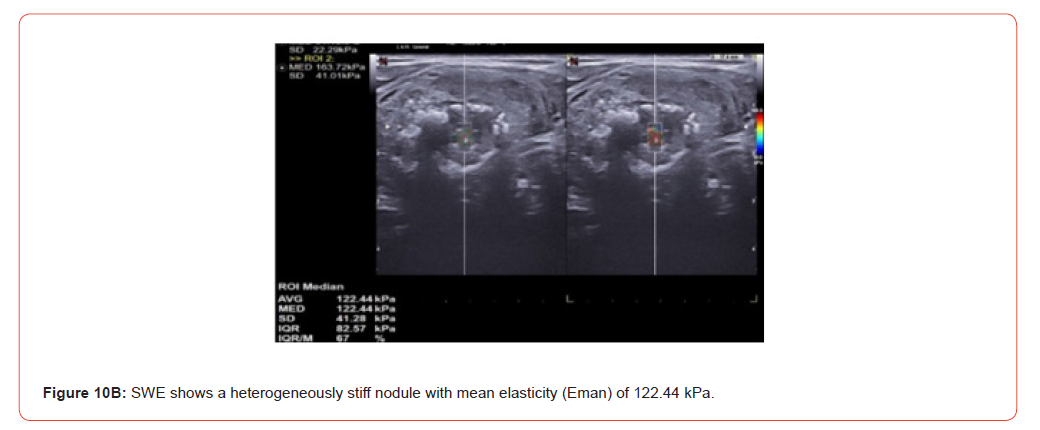

Figure 9 and 10 show representative case of benign and malignant thyroid nodule.